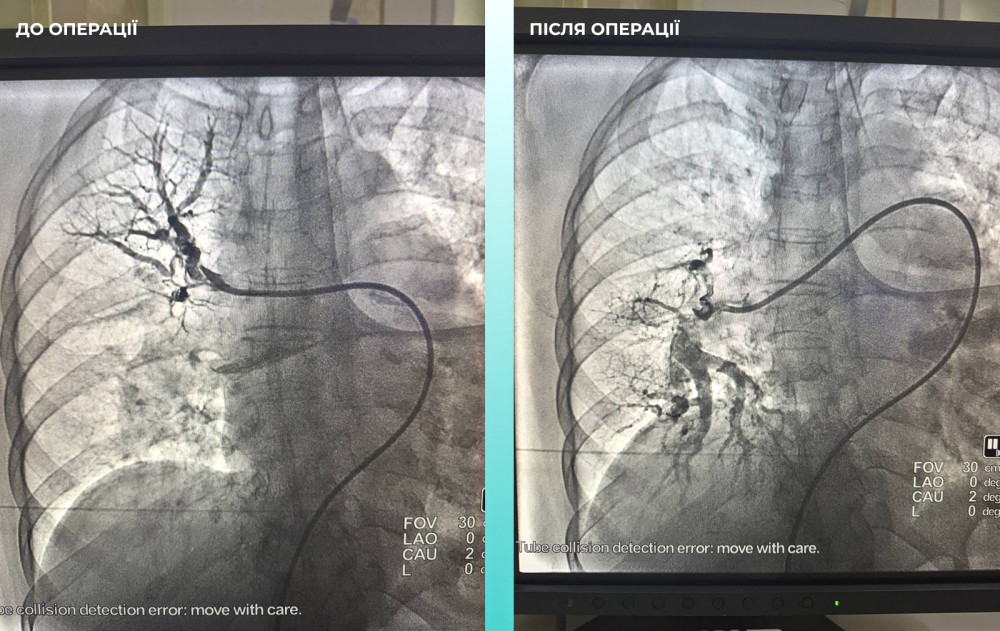

Кроме того, медики заметили, что пациентке сложно дышать, что побудило их провести дополнительное исследование легких. Диагноз осложнился тромбоэмболией легочной артерии.

Мультидисциплинарная команда врачей приняла сложное, но жизненно необходимое решение — провести одновременную тромбектонию на мозговой и легочной артериях.

Операция прошла успешно, и пациентка сейчас чувствует себя значительно лучше: она в сознании и уже начинает двигать конечностями.